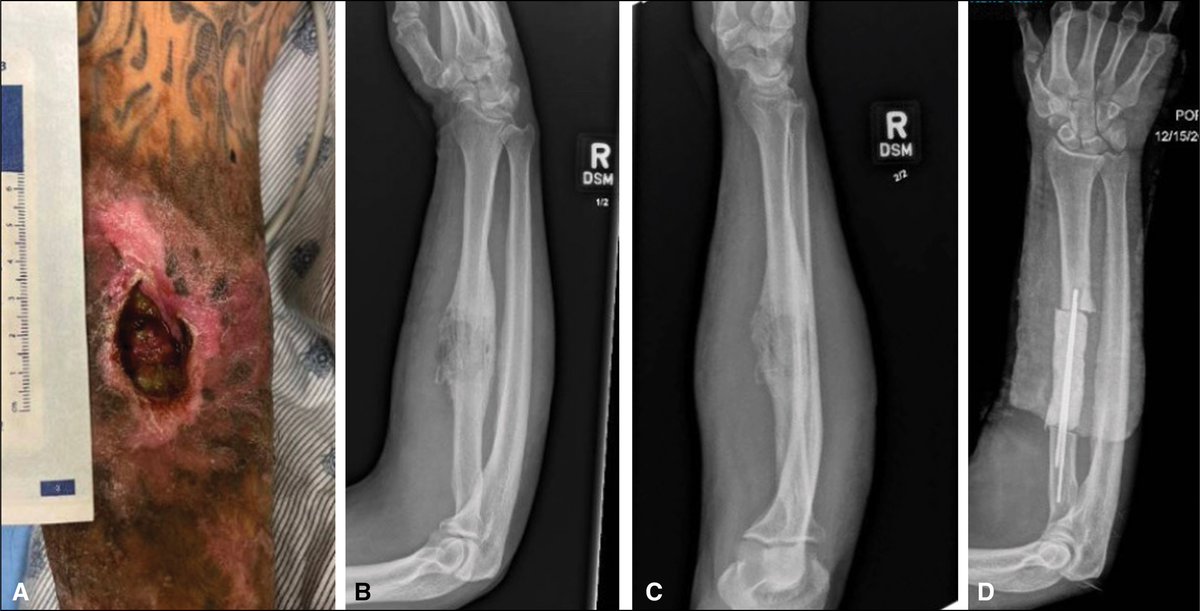

Exploring the latest research: Management of Xylazine-Induced Soft Tissue Necrosis β A Review of 20 cases https://t.co/UnmmT9Cs0y